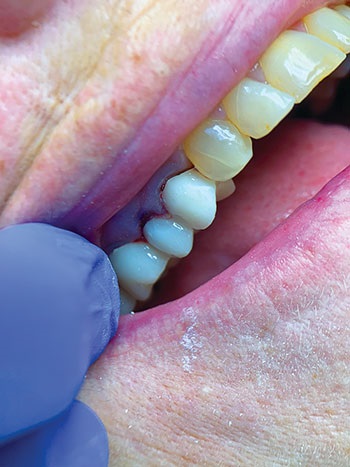

An initial clinical exam revealed an 8 mm periodontal pocket depth on the distal of maxillary #13. The presence of slight bleeding and purulence was evident during periodontal probing. A periapical X-ray showed a loss of epithelial attachment and pocketing, which led to endodontic involvement in tooth #13 (Figs. 1 and 2). The tooth also exhibited early grade 2 mobility. Contributing factors included pain on vertical percussion, indicating primary periodontal with secondary endodontic involvement.

Fig. 2: Pre-operative clinical exam.